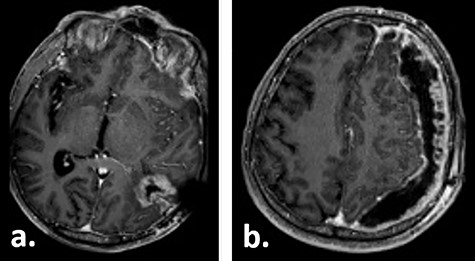

Fifteen weeks after tumour resection and 4 weeks after hygroma evacuation, the patient presented again with concentration loss, fatigue and a moderate right-sided hemiparesis. A new CT scan revealed a strongly progressive subdural hygroma with a 3-mm-thick subdural membrane. The hygroma was evacuated through the same burr hole; however, due to an unsatisfying hygroma regression, a subduro–peritoneal shunt for permanent hygroma drainage was implanted subsequently. During these both procedures, a thick greyish subdural membrane was noticed, but no tissue samples were taken. Despite the volume reduction of the hygroma, its membrane still caused a considerable mass effect. Few days after the last surgical procedure, a cerebral MRI was performed following the tumour follow-up protocol. On this imaging, the subdural membrane over the left hemisphere presented as an inhomogeneous contrast-enhancing lesion with irregular contours (Fig. 3).

Gadolinium-enhanced T1-weighted axial MRI of the patient 16 weeks after tumour resection demonstrating the resection cavity (a) and progressive subdural fluid collection with the newly occurred contrast-enhancing membrane (b).